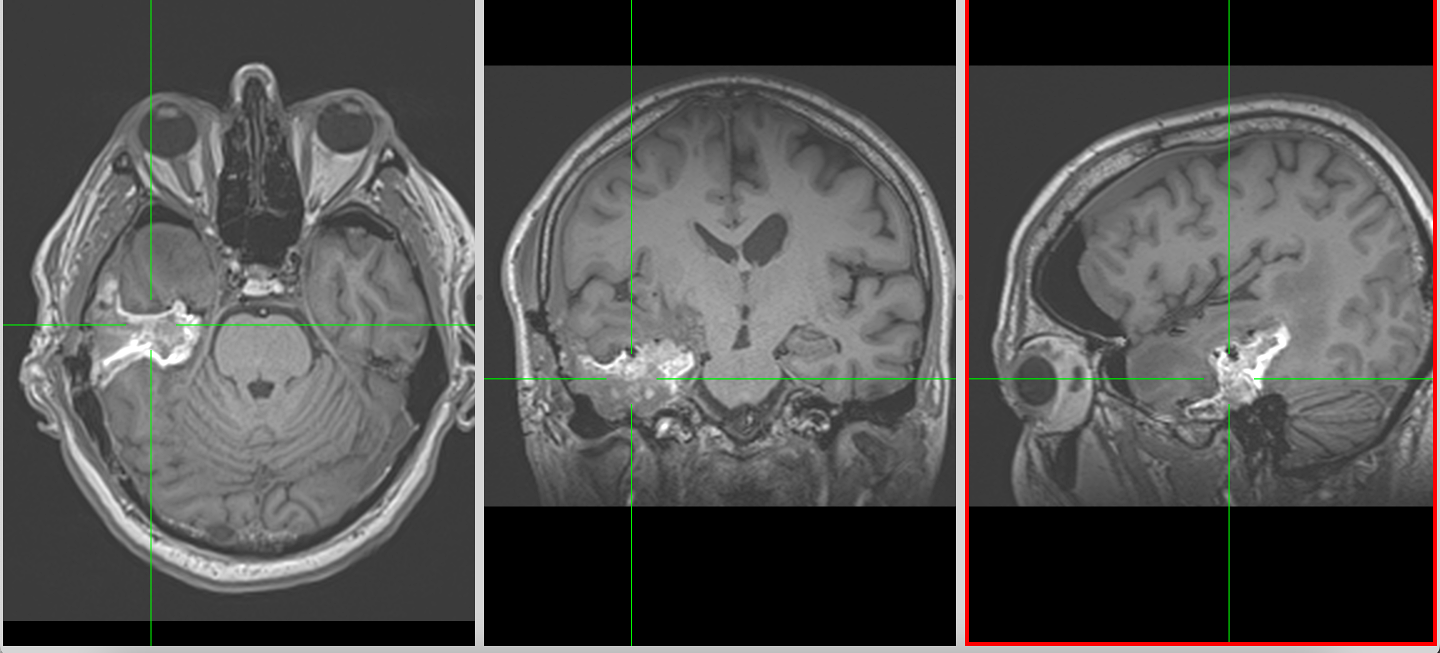

RMN-ul cerebral este standardul diagnostic, dar trebuie interpretat în context.

Pe lângă secvențele convenționale, tehnicile avansate aduc informații suplimentare:

- perfuzia evidențiază angiogeneza tumorală

- spectroscopia reflectă metabolismul celular

- DTI (tractografia) arată relația cu tracturile din substanța albă

Cu toate acestea, niciuna dintre aceste metode nu poate delimita complet infiltrarea microscopică. De aceea, planificarea chirurgicală și terapeutică trebuie să țină cont de această limitare.